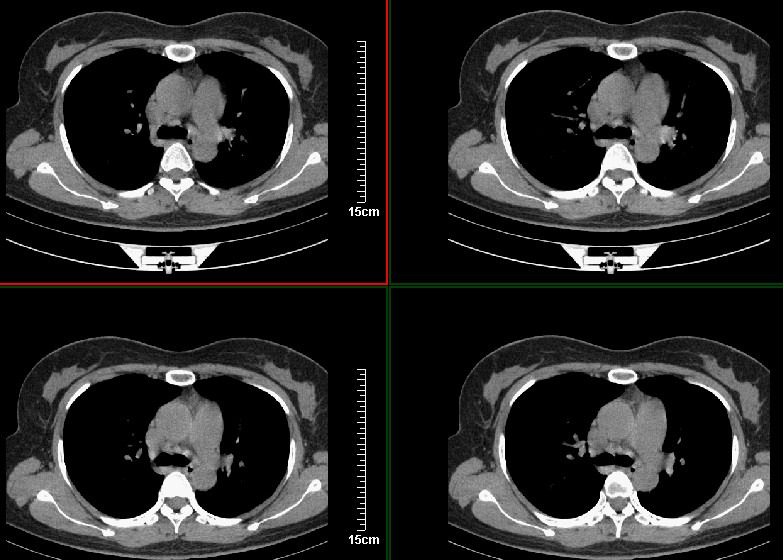

一周之后 复查结果 5mm扫描 40多岁 我们医院的护士

病史?1.首先考虑左肺上叶占位(ca可能);

2.继发型肺tb?

3.单纯感染不除外。

左上肺周围型肺癌可能性大,楼主片子太小

考虑左肺上叶周围型肺癌可能性大.

左肺上叶肿块,肺窗周围有“晕征”,纵隔窗有毛刺,临床资料???只能考虑占位???